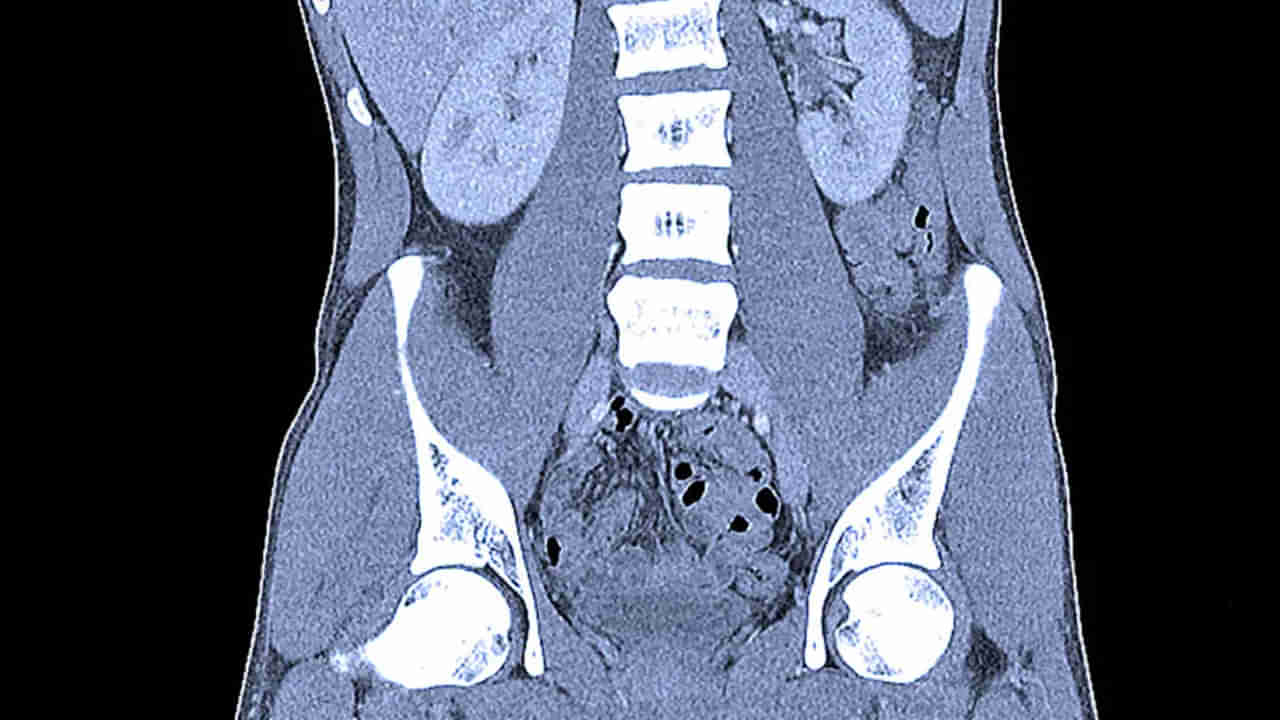

ఆ వ్యక్తికి పుట్టినప్పటి నుంచి మెంటల్ బ్యాలెన్స్ సరిగ్గా లేదు. మాటలు మాట్లాడలేడు. చెవులు కూడా సరిగ్గా వినపడవు. కాగా ఇటీవల కడుపులో విపరీతమైన నొప్పి రావడంతో.. కుటుంబ సభ్యులు అతడిని ఆస్పత్రికి తీసుకొచ్చారు. ఈ క్రమంలో టెస్టులు చేసిన డాక్టర్లు స్టన్ అయ్యారు. అతని పొట్టలో అనేక వ్యర్థాలు ఉండటం చూసి.. నిర్ఘాంతపోయారు. రోగి బాధను బయటకు చెప్పలేక.. ఎంత మదనపడుతున్నాడో అర్థం చేసుకుని.. వెంటనే ఆపరేషన్ చేశారు. అతని కడుపు నుంచి 2 హెన్నా కోన్లు, 15 ప్లాస్టిక్ స్ట్రాస్, దాదాపు 62 చెక్క ముక్కలను రిమూవ్ చేశారు. వివరాల్లోకి వెళ్తే… గుజరాత్(Gujarat) వీరావల్(Veraval)లోని మాల్దా ఏరియాకు చెందిన.. అర్జున్ చంద్పా(40)కు బై బర్త్ మతిస్థిమితం సరిగ్గా లేదు. దీంతో ఫ్యామిలీ మెంబర్స్ అతడిని జాగ్రత్తగా చూసుకుంటూ వస్తున్నారు. అయితే చాలా రోజుల నుంచి చంద్బా ముభావంగా ఉంటున్నాడు. అప్పుడప్పుడు కడుపు నొప్పితో విలవిల్లాడుతున్నాడు. దీంతో బంధువులు జునాగఢ్(Junagadh) గవర్నమెంట్ ఆస్పత్రికి తీసుకెళ్లారు. బాధితుడికి సీటీ స్కాన్ చేసి కడుపులో అనేక వస్తువులు ఉన్నట్లు గుర్తించారు. పరిస్థితి విషమించికముందే ఆపరేషన్ చేయాలని డిసైడయ్యారు. 2 గంటల పాటు శస్త్రచికిత్స నిర్వహించి.. అతని కడుపు నుంచి 15 ప్లాస్టిక్ స్ట్రాలు, 2 హెన్నా కోన్లు, 62 చెక్కముక్కలు బయటకు తీశారు. ఇవన్నీ అతడి కడుపులో ఒక గడ్డ మాదిరిగా మారాయి. సరైన అవగాహన లేక బాధితుడు వాటిని మింగి ఉంటాడని అని వైద్యులు తెలిపారు.